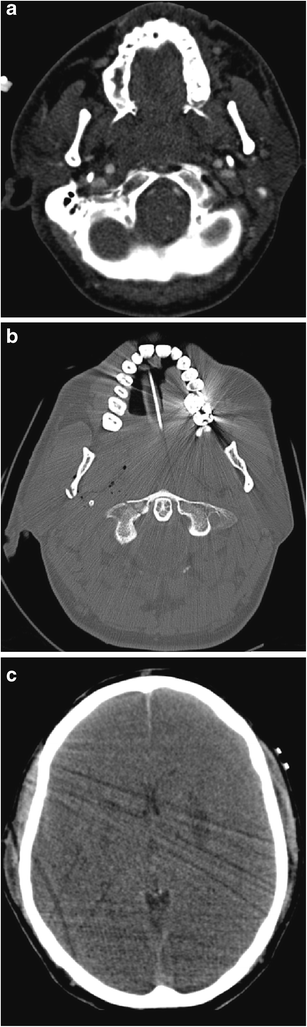

a Coronal reformatted non-contrast CT brain image of a 34-year-old man who sustained a penetrating knife injury to the left zone 2 of the neck requiring emergency surgical neck exploration prior to imaging assessment because of catastrophic haemorrhage. Therefore, pre-treatment CT and MDCTA were not performed because of the clinically evident active life-threatening haemorrhage on arrival in the emergency department. The non-contrast CT brain assessment was performed immediately prior to the post-operative MDCTA (b) and demonstrates acute thromboembolic “malignant” left anterior circulation infarction: there is already ischaemic demarcation of both the left middle and anterior cerebral artery territories with severe subfalcine herniation and midline shift; hyperdense thromboembolus is evident in the left middle cerebral artery (arrows) and proximal left anterior cerebral artery. b Axial image of MDCTA of the same patient as in a performed immediately post-operatively following internal carotid artery repair reveals a tail of extensive intraluminal thrombus extending distally from the site of vessel injury and repair (arrow). c Axial non-contrast CT brain of the same patient as in a and b performed 48 h later. The patient has undergone interval emergency left decompressive hemicraniectomy: the left anterior circulation low attenuation infarction is more established and the significant mass effect, subfalcine herniation and intracranial pressure related to swollen oedematous parenchyma have been ameliorated by hemicraniectomy. Unfortunately, brain-stem death was confirmed 12 h later